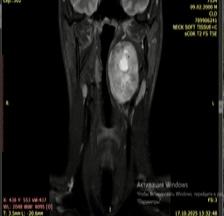

После эндоскопического осмотра в отделении ВДП, пациенту в отделении лучевой диагностики центра было выполнено МРТ исследование области шеи, при котором было выявлено образование размером 7 см х 5 см, располагающееся в парафарингеальной области, (рис. 1, 2)